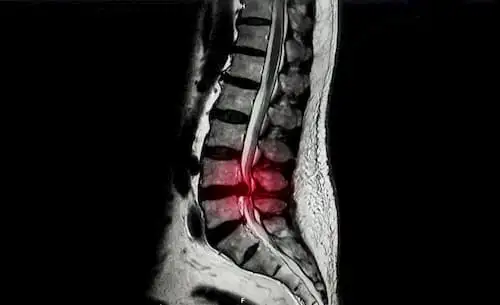

Дегенеративные заболевания поясничного отдела позвоночника представляют собой серьезную проблему для здравоохранения, что стимулирует поиск передовых хирургических подходов. Примером перспективного хирургического подхода является косой поясничный межтеловой спондилодез (OLIF), но остается открытым вопрос о том, какая из двух техник эффективнее: OLIF с передней винтовой фиксацией (OLIF-AF) или OLIF с задней педикулярной фиксацией (OLIF-PF). Цель данного исследования состояла в сравнении эффективности этих двух техник.